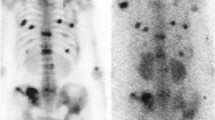

Painful metastatic bone lesions with osteoblastic response, as confirmed by areas of intense uptake on radionuclide bone scans.

The patient medical history should be obtained with special emphasis on severity, localization and duration of bone pain and its response to other treatment modalities. Prior to the administration of strontium-89, samarium-153 or phosphorus-32, the patient should have had a recent bone scan (within the previous 8 weeks) documenting increased osteoblastic activity at the painful sites. Radiographs demonstrating osteosclerotic lesions are not adequate, as increased bone density does not always result in increased uptake on radionuclide imaging. Abnormalities on the bone scan must be correlated with an appropriate physical examination to exclude other causes of chronic pain, which would be unlikely to respond to treatment using bone-seeking radiopharmaceuticals. Neurogenic pain and pathological fractures should be specifically excluded. Bone scintigraphic abnormalities should also be correlated with the physical examination and other imaging studies to ascertain that osseous or soft-tissue abnormalities, which might cause cord or nerve compression or pathological fractures, are not present. The only indication for the use of strontium-89, samarium-153 or phosphorus-32 in these circumstances would be in conjunction with local treatment, either radiation therapy or surgical intervention, if there are other sites of painful bone metastases.